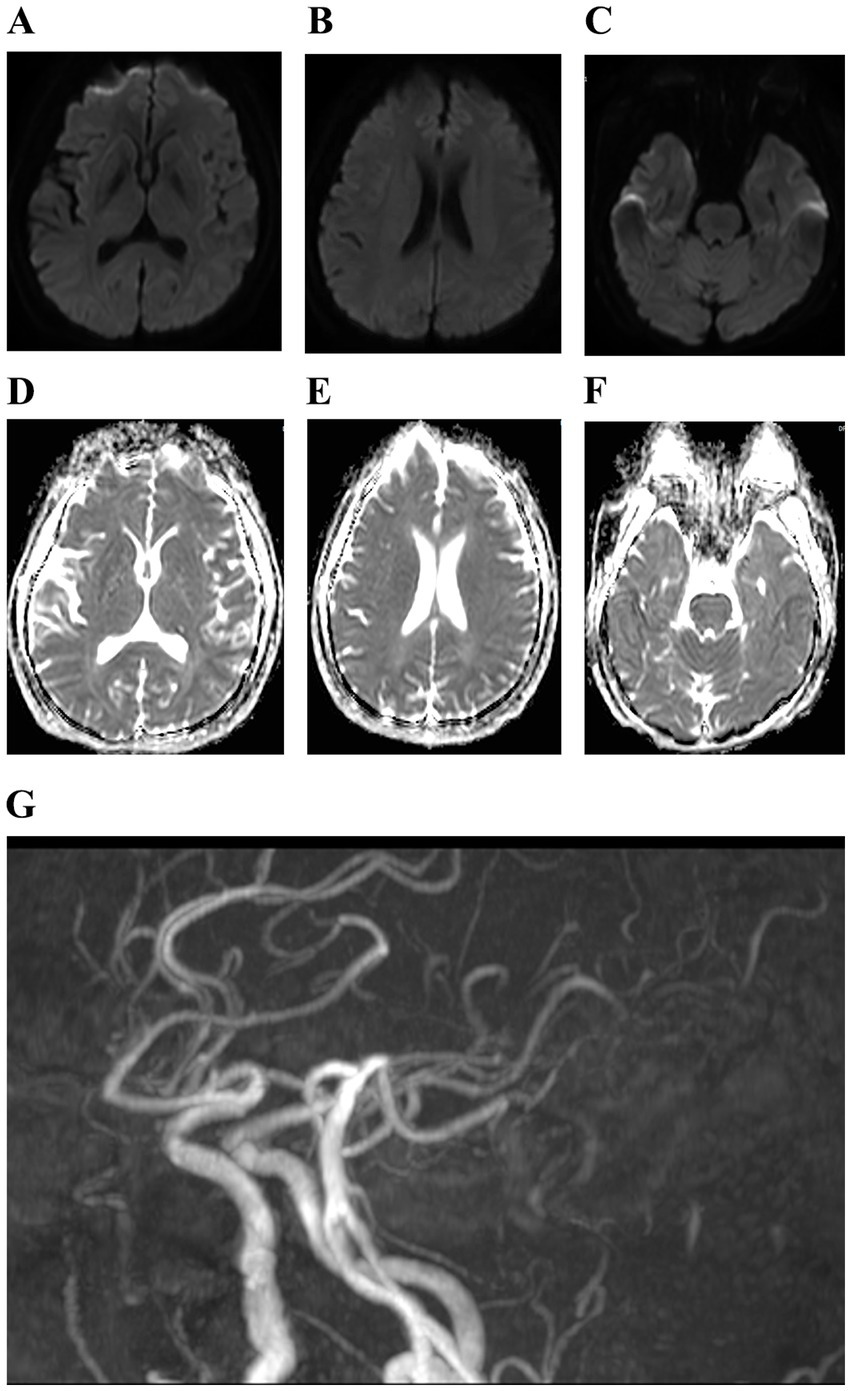

Figure 3

(A–G) Cranial magnetic resonance showed mild cerebral atrophy and cerebral atherosclerosis.

Figure 1

On admission, the patient had a body temperature of 38.8 °C, a heart rate of 112 beats per minute, a respiration rate of 20 beats per minute, and a blood pressure of 151/76 mmHg. Cardiopulmonary and abdominal examinations did not show any obvious abnormalities. A scar was observed between the index finger and thumb on the back of the right hand. Neurological examination showed clear mentation, articulation, and normal gross tests of higher neurological function. Both pupils were equal in size and round, with a diameter of about 3.0 mm, sensitive to light. Both eyes had adequate movement in all directions. The extension of the tongue showed centered teeth and normal pharyngeal reflexes. The muscle tone in the extremities was normal. The muscle strength of the left limb, right lower limb, and proximal part of the right upper limb was normal; however, the distal right upper limb was grade 0. The Babinski sign was negative, and meningeal irritation was also negative. Laboratory tests revealed the following blood routine indicators: white blood cell count at 9.39 × 109/L, neutrophils at 7.19 × 109/L, monocytes at 0.99 × 109/L, eosinophils at 0.00 × 109/L. The percentage of neutrophils, lymphocytes, and monocytes in the blood were 76.6, 12.8, and 10.5%. No abnormalities were detected in coagulation function, procalcitonin, liver function, renal function, electrolytes, cardiac enzymes, blood cultures, syphilis antibodies, viral hepatitis C antibodies, and human immunodeficiency virus antibodies. A CT scan of the lungs indicated no abnormality. The patient was prescribed enteric-coated aspirin tablets, clopidogrel tablets for antiplatelet aggregation, and statins for lipid regulation. Following admission to the hospital, the patient exhibited a progressive decline in muscle strength. The strength of the proximal muscle in the right lower and right upper extremity was assessed as normal, while the distal muscle strength of the right upper extremity was rated at grade 0. Proximal muscle strength of the left upper extremity was evaluated at grade 4, and its distal strength recorded as grade 0. The left Babinski’s sign was positive, while the right Babinski’s sign was negative. Lumbar puncture showed a CSF pressure of 300 mmH2O; the CSF nucleated cell counts was 25 × 106/L, of which 0.92% were single nucleated cells and 0.08% were multiple nucleated cells. The CSF protein concentration was 571 mg/L. Rabies virus sequences were detected by CSF metagenomics sequencing. The mNGS employed the Probe-Capture Metagenomics method, and the total number of reads detected was 875,729. Finally, nine rabies virus reads were identified through bioinformatic analysis (Supplementary Table 1). Cranial magnetic resonance imaging, diffusion tensor imaging, and magnetic resonance angiography showed no abnormalities (Figure 3). On November 9, 2023, the patient suffered sudden respiratory cardiac arrest and fell into a deep coma, and was immediately given transoral intubation balloon assisted ventilation. The patient died on November 11, 2023, after an unsuccessful rescue effort. The chronological timeline of clinical events in the present case is shown in Table 1. The patient did not exhibit characteristic hydrophobia during the course of the disease. The patient was ultimately diagnosed with paralytic rabies.